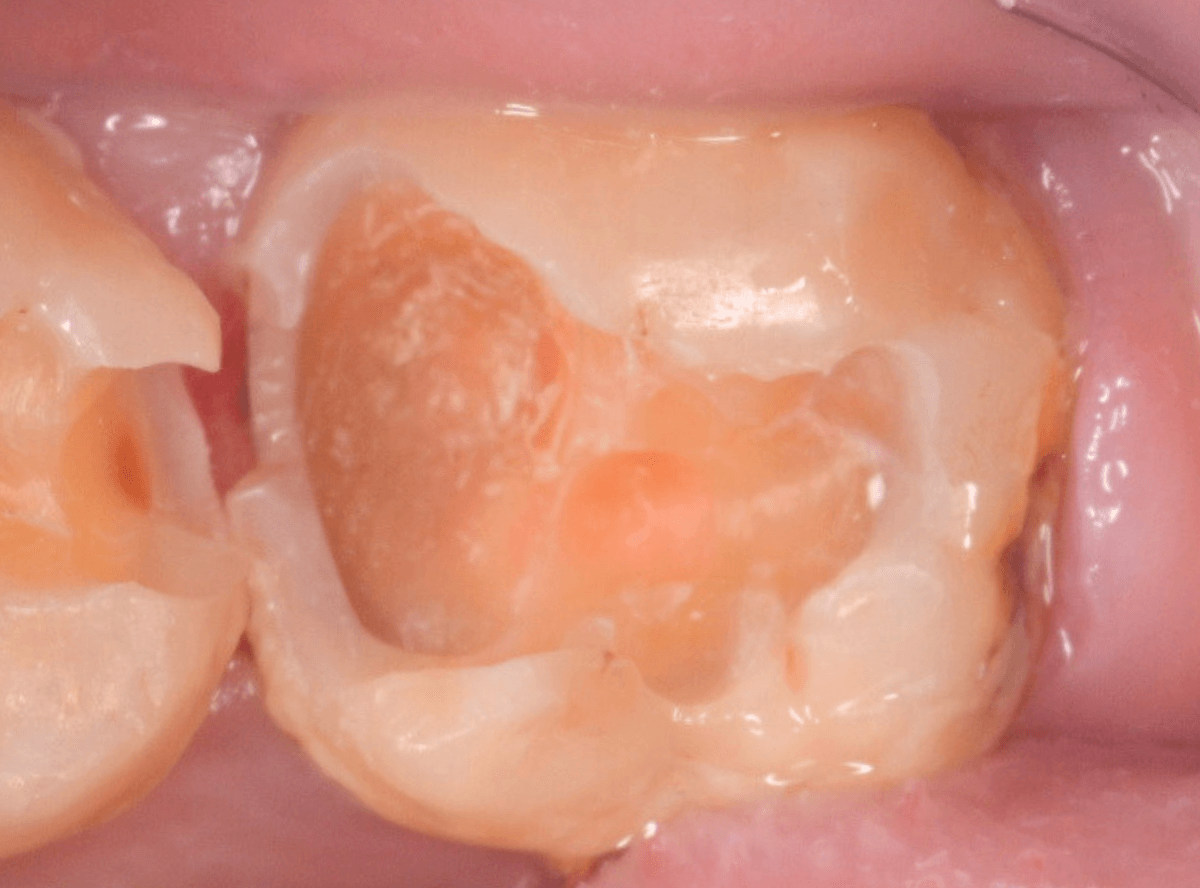

金属のつめ物を外したところです。

この白いセメントの中に虫歯があると思われます。

セメントを除去したところです。

赤く染まっている部分が虫歯です。

真っ赤ですね(^^;)

慎重に虫歯を除去していきましたが、まだ薄く染まっています。

もう少し除去する必要があります。

全ての虫歯が取れました、かなり深い神経まで近い虫歯でした。